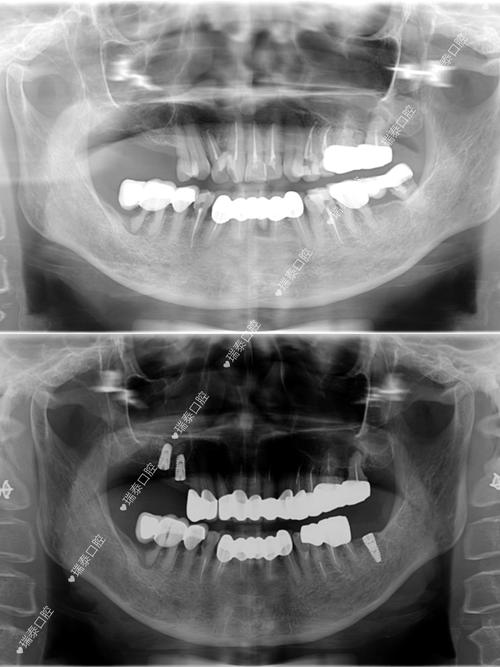

这是种植成功的基础,医生会通过口腔临床检查、CBCT影像、全景片等,评估患者的牙槽骨高度、宽度、密度,以及邻牙健康状况、全身性疾病(如糖尿病、高血压)控制情况,对于骨量不足者,可能需先进行植骨或上颌窦提升术,等待3-6个月骨结合后再进入下一步。

从技术层面看,福州市主流种植牙技术已与国际接轨,数字化种植是当前趋势,通过CBCT(锥形束CT)获取口腔三维数据,结合口内扫描仪生成数字化模型,医生可在术前模拟种植过程,制定个性化方案,针对牙槽骨条件不佳的患者,骨增量技术(如植骨、上颌窦提升)的应用也较为成熟,为种植体提供稳固的“地基”,即刻种植(拔牙后立即植入种植体)、All-on-4/6全口半口即刻负重等技术,可缩短治疗周期,部分患者可实现“当天种牙、当天戴冠”,快速恢复咀嚼功能。